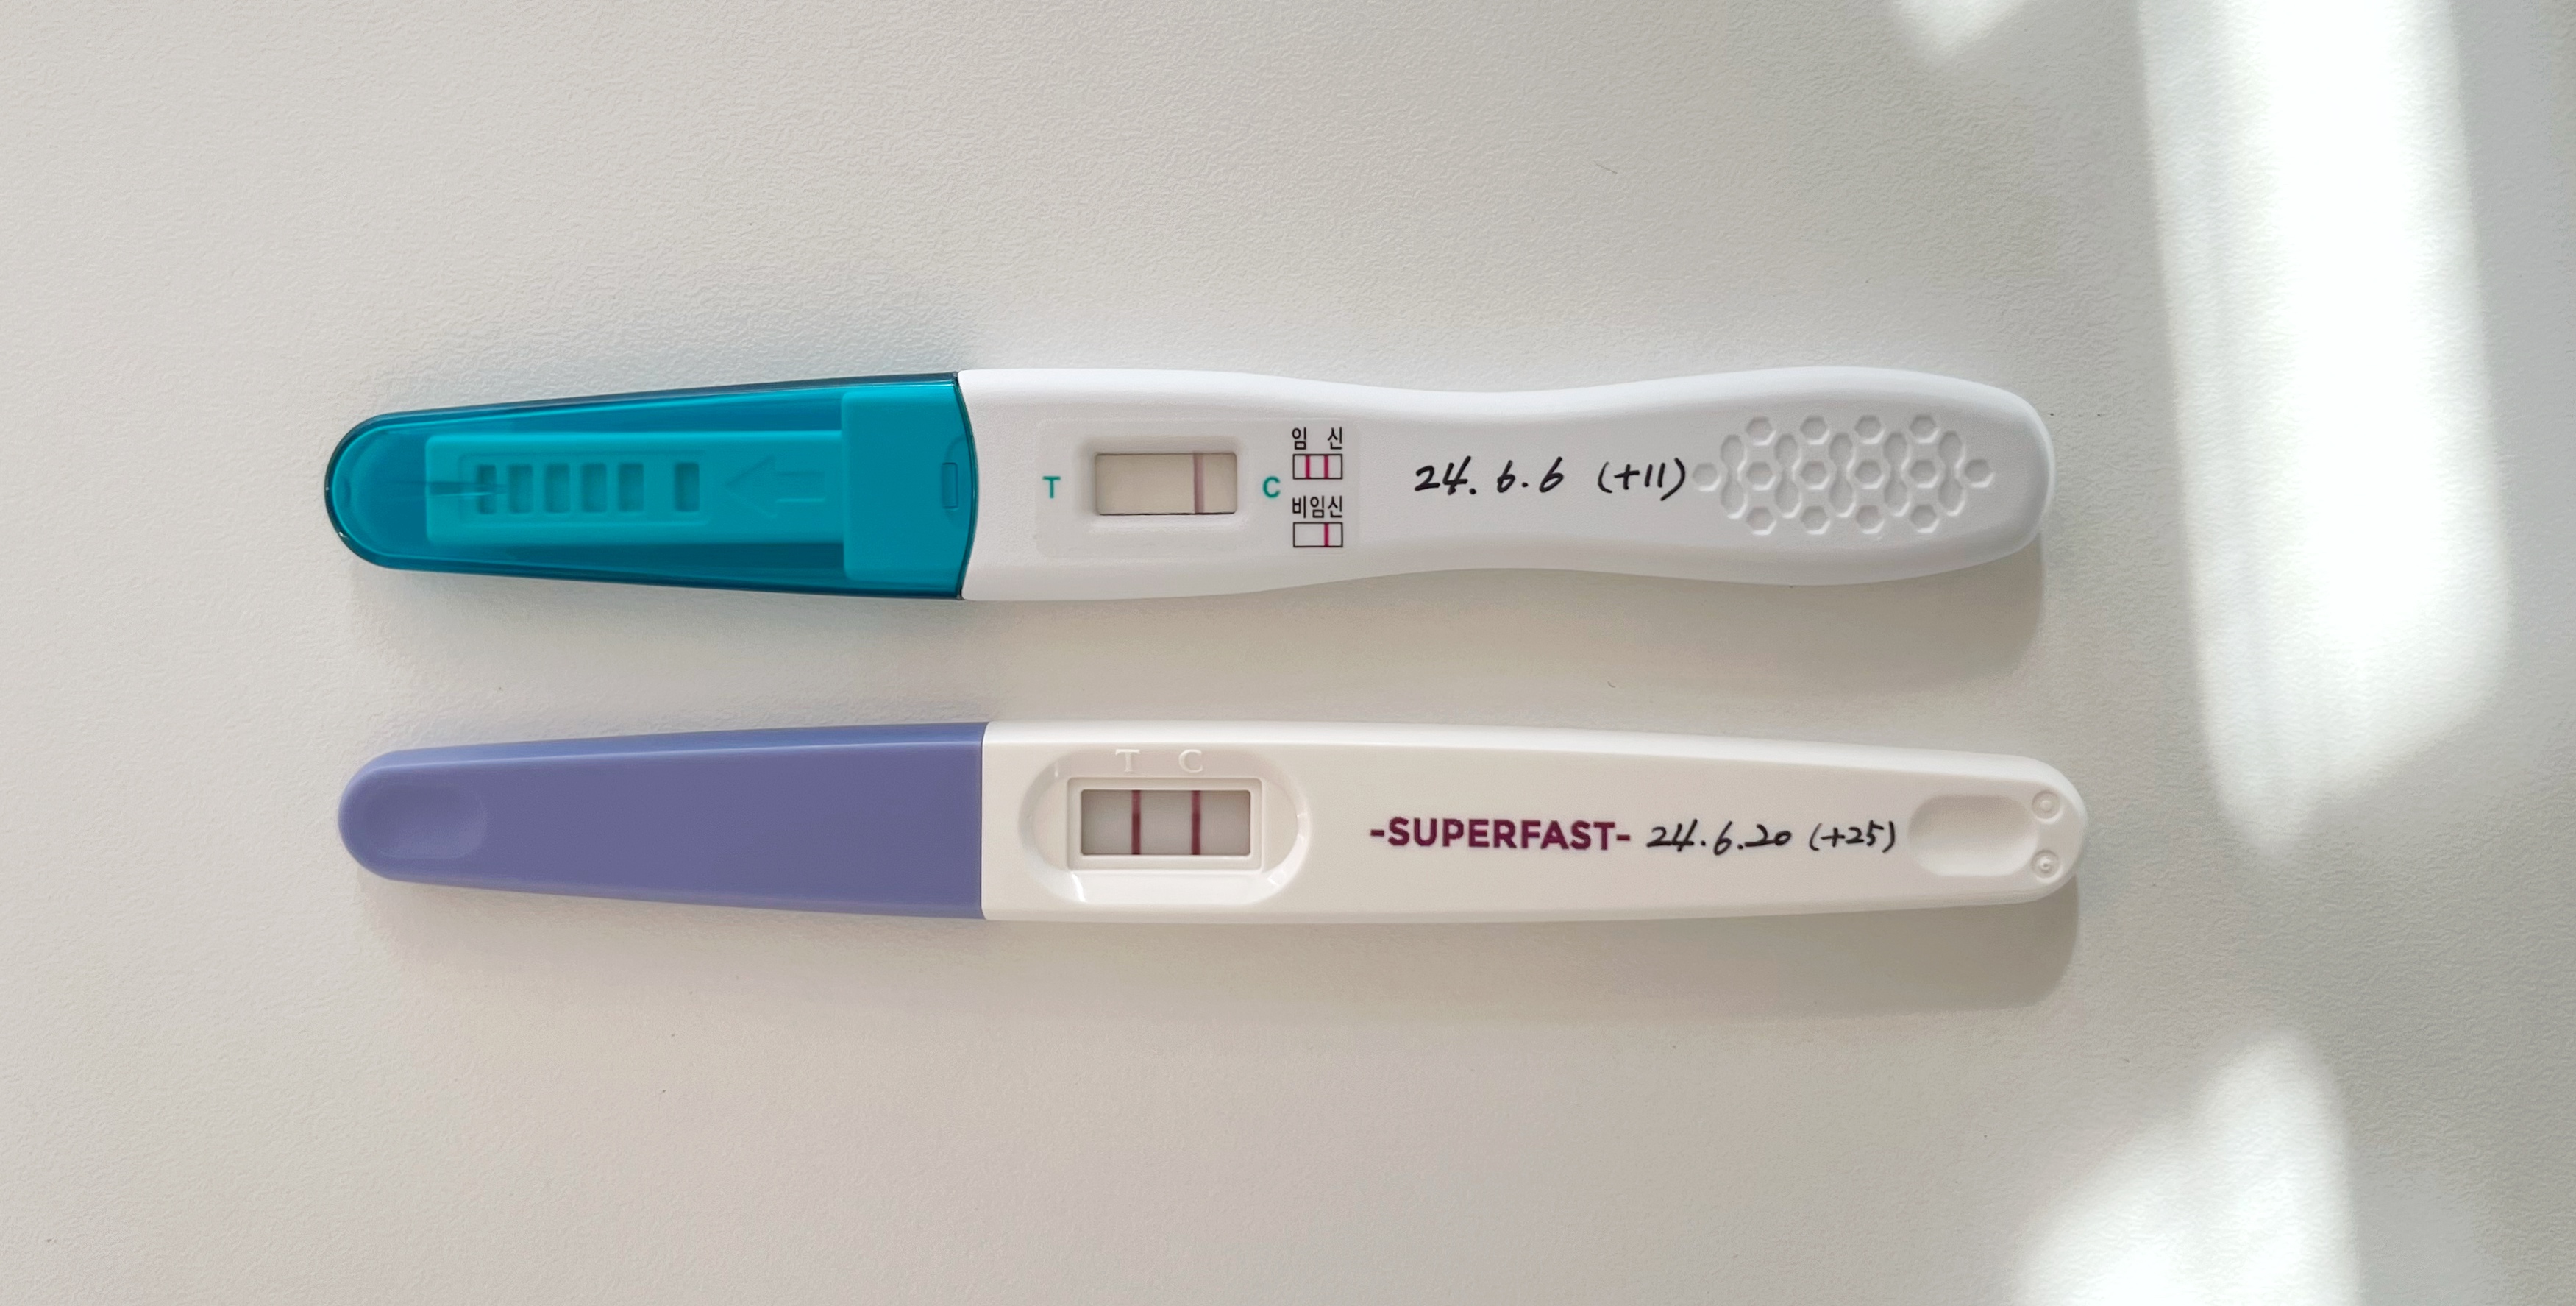

23일차, 25일차에도 임테기를 해보았는데

사실 이제 임테기는 더 의미 없는 것 같아서 25일차를 마지막으로 했다.ㅎㅎ

배란 11일차, 25일차 임테기 비교